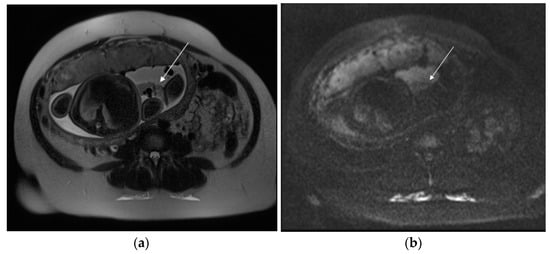

When US is indeterminate, MRI or CT can reveal an ill-defined mass with multiple serpiginous and ectatic vessels in the myometrium and parametrium, connecting to the uterine arteries: this finding, clearly depicted on MR-angiography, corresponds to the hypervascular areas on Color Doppler US, representing a hallmark of uterine AVMs [8]. In congenital AVMs, several arterial feeders may be detected, with a more prominent nidus, whereas acquired types are typically supplied by a single intramural and hypertrophied feeding artery draining directly in a single parauterine vein [111]. Other MRI features of AVM include bulky uterus, focal disruption of the junctional zone, and flow-void artifacts (Figure 10).